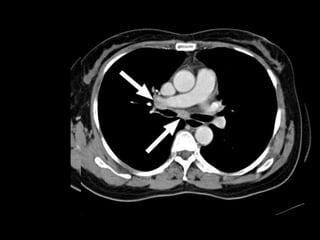

Lymphatic Drainage Thoracic

Contents

 Tracheobronchial nodes – 5 groups

 Paratracheal

 Superior tracheobronchial

 Inferior tracheobronchial

 Bronchopulmonary

 Pulmonary

 Left & right bronchomediastinal trunks drain

into thoracic duct & right lymphatic duct

Paratracheal Paratracheal

Inferior

tracheobronchial

Superior tracheobronchial

Bronchiopulmonary

Pulmonary